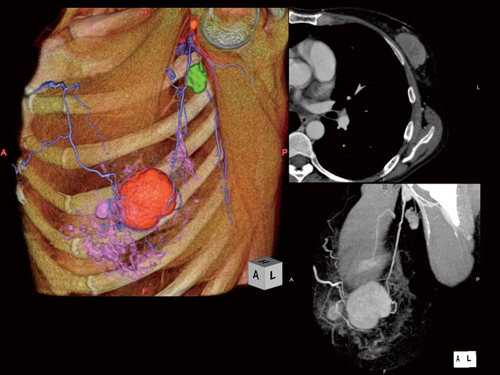

術前においては,歪みのないVR像により腫瘍とその近傍の脈管,リンパ節などのマッピングを,あらかじめ術者に提供することが可能です(図1)。

図1 乳房CT画像

0.5mmスライス撮影,さらにはAECを使用。術前検査として原発巣の乳頭からの距離,肋骨に対する位置情報を正確に把握できます。